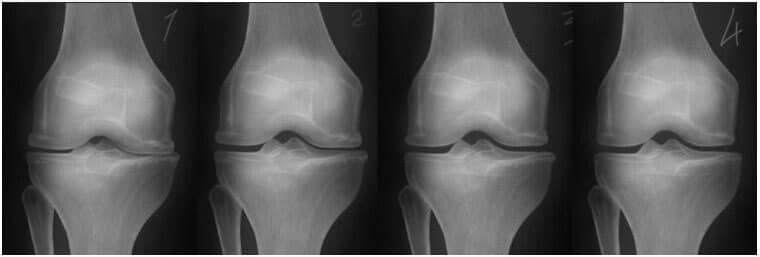

- Imaginea radiografică de mai jos prezintă un model tipic de regenerare a articulației genunchiului.